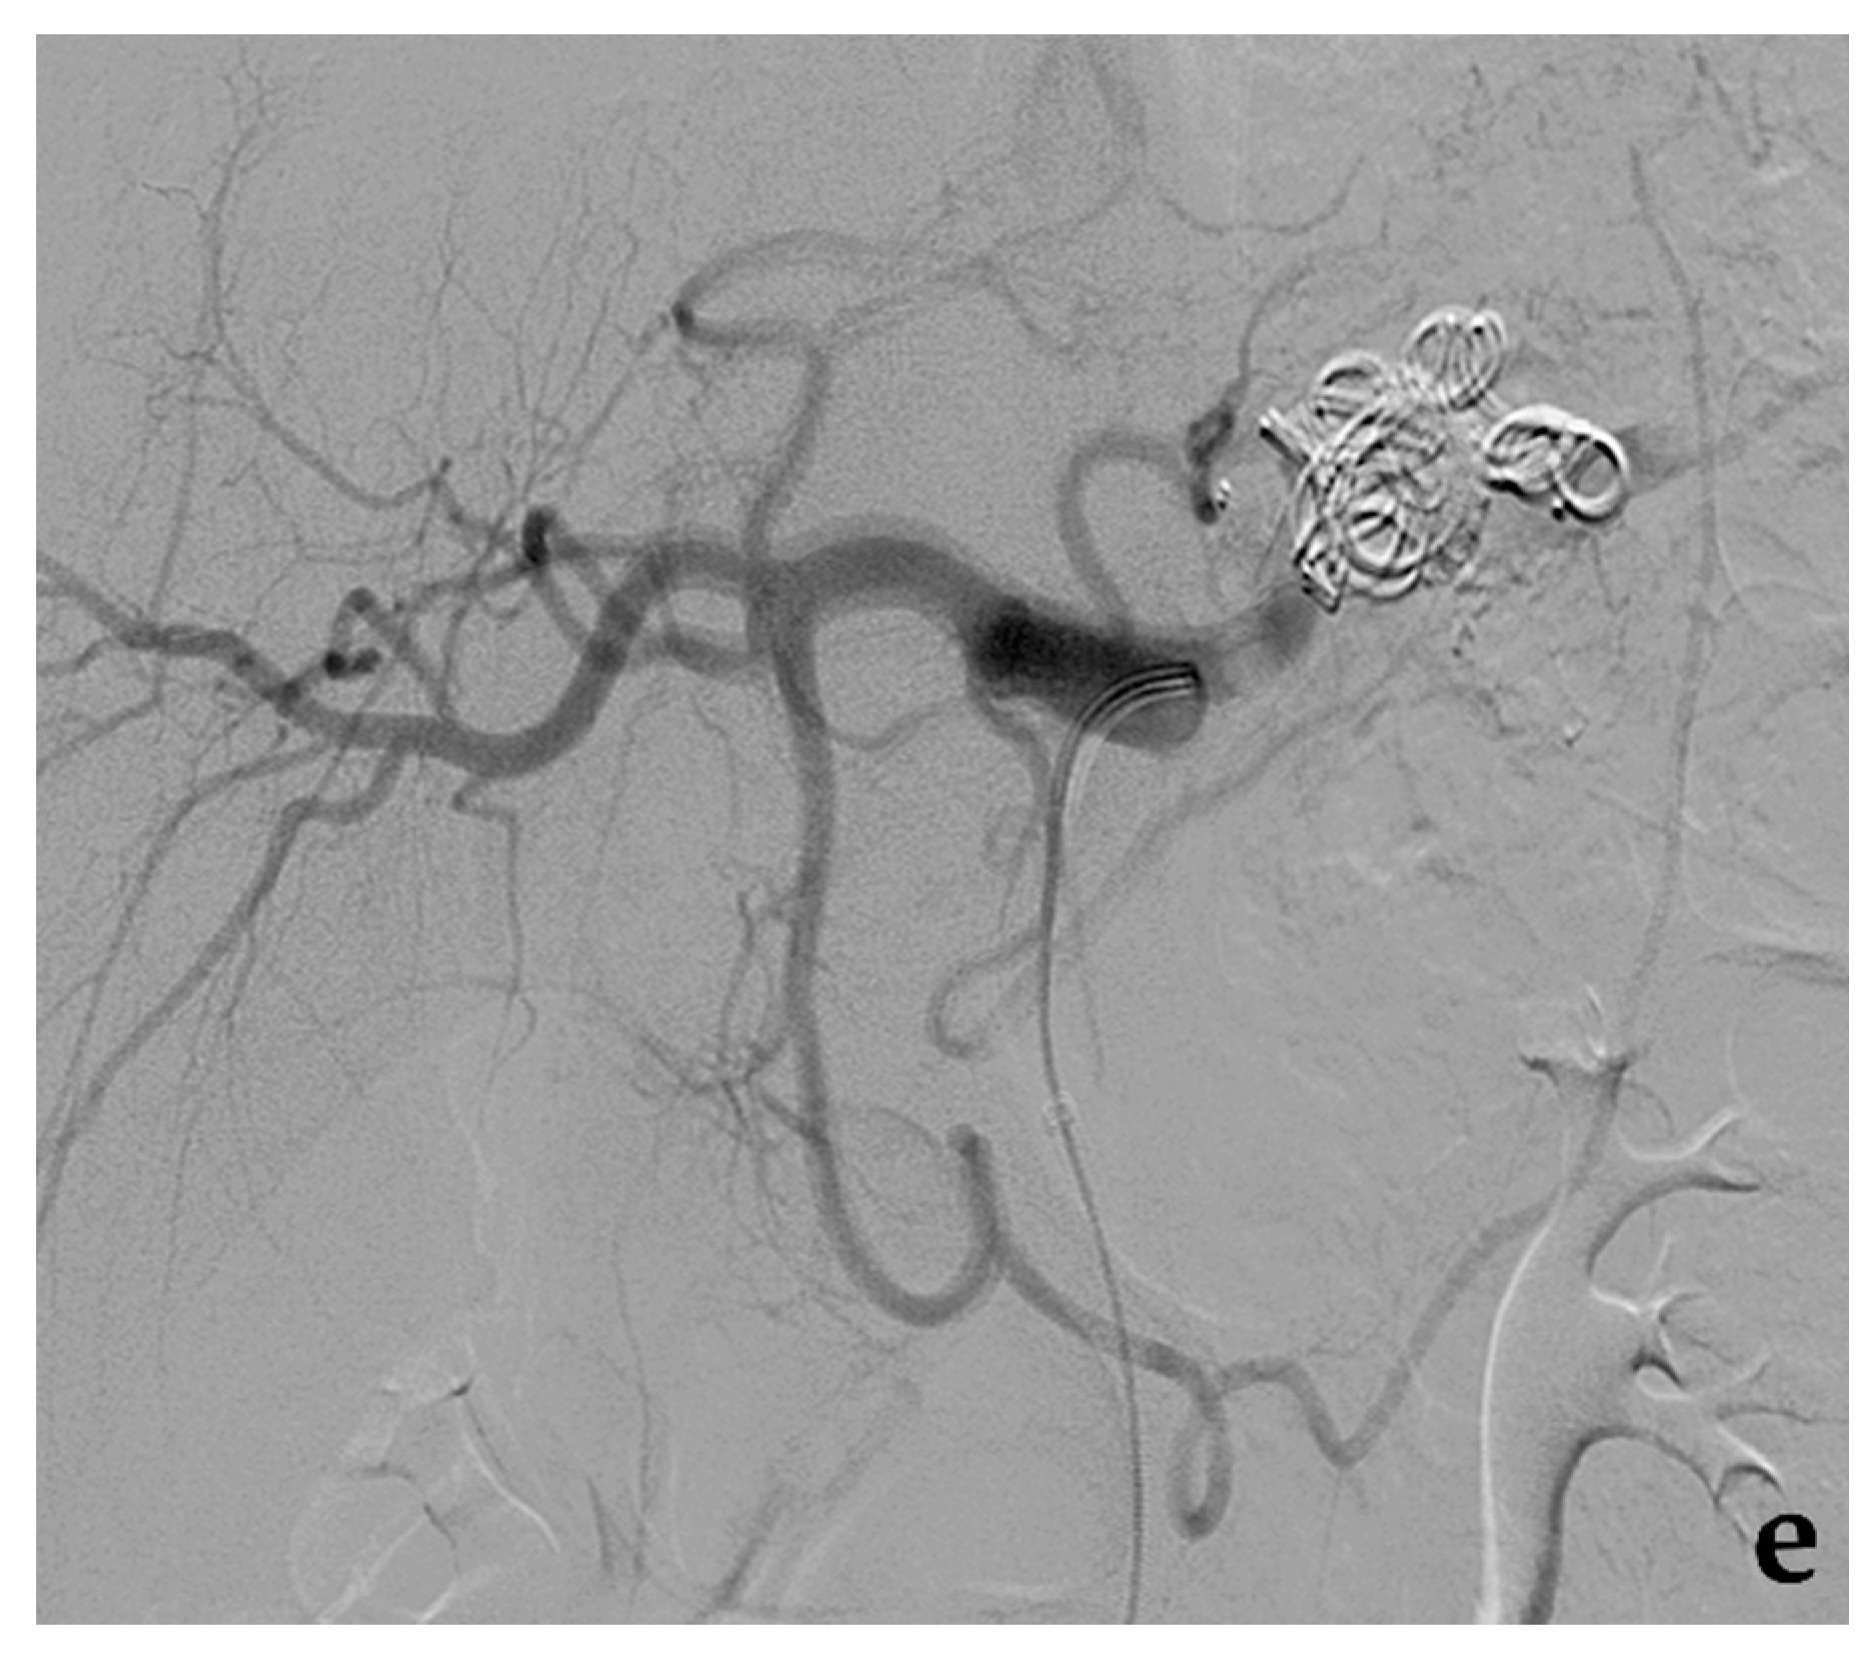

3.2. Stent-Assisted Coil Embolization

- Wei, X.; Sun, Y.; Wu, Y.; Li, Z.; Zhu, J.; Zhao, Z.; Feng, R.; Jing, Z. Management of wide-based renal artery aneurysms using non covered stent-assisted coil embolization. J. Vasc. Surg. 2017, 66, 850–857. [Google Scholar] [CrossRef]

- Secco, G.; Chevallier, O.; Falvo, N.; Guillen, K.; Comby, P.O.; Mousson, C.; Majbri, N.; Midulla, M.; Loffroy, R. Packing technique with or without remodeling for endovascular coil embolization of renal artery aneurysms: Safety, efficacy and mid-term outcomes. J. Clin. Med. 2021, 10, 326. [Google Scholar] [CrossRef]

- Ma, T.; He, Y.; Zhong, W.; Luo, G.; Li, Q.; Wang, Z.; Zhang, H.; Wu, Z.; Qiu, C. Mid-term results of coil embolization alone or stent-assisted coil embolization for renal artery aneurysms. Ann. Vasc. Surg. 2021. [Google Scholar] [CrossRef]

- Bracale, U.M.; Narese, D.; Ficarelli, I.; De Laurentis, M.; Spalla, F.; Dinoto, E.; Vitale, G.; Solari, D.; Bajardi, G.; Pecoraro, F. Stent-assisted detachable coil embolization of wide-necked renal artery aneurysms. Diagn. Interv. Radiol. 2017, 23, 77–80. [Google Scholar] [CrossRef] [PubMed]